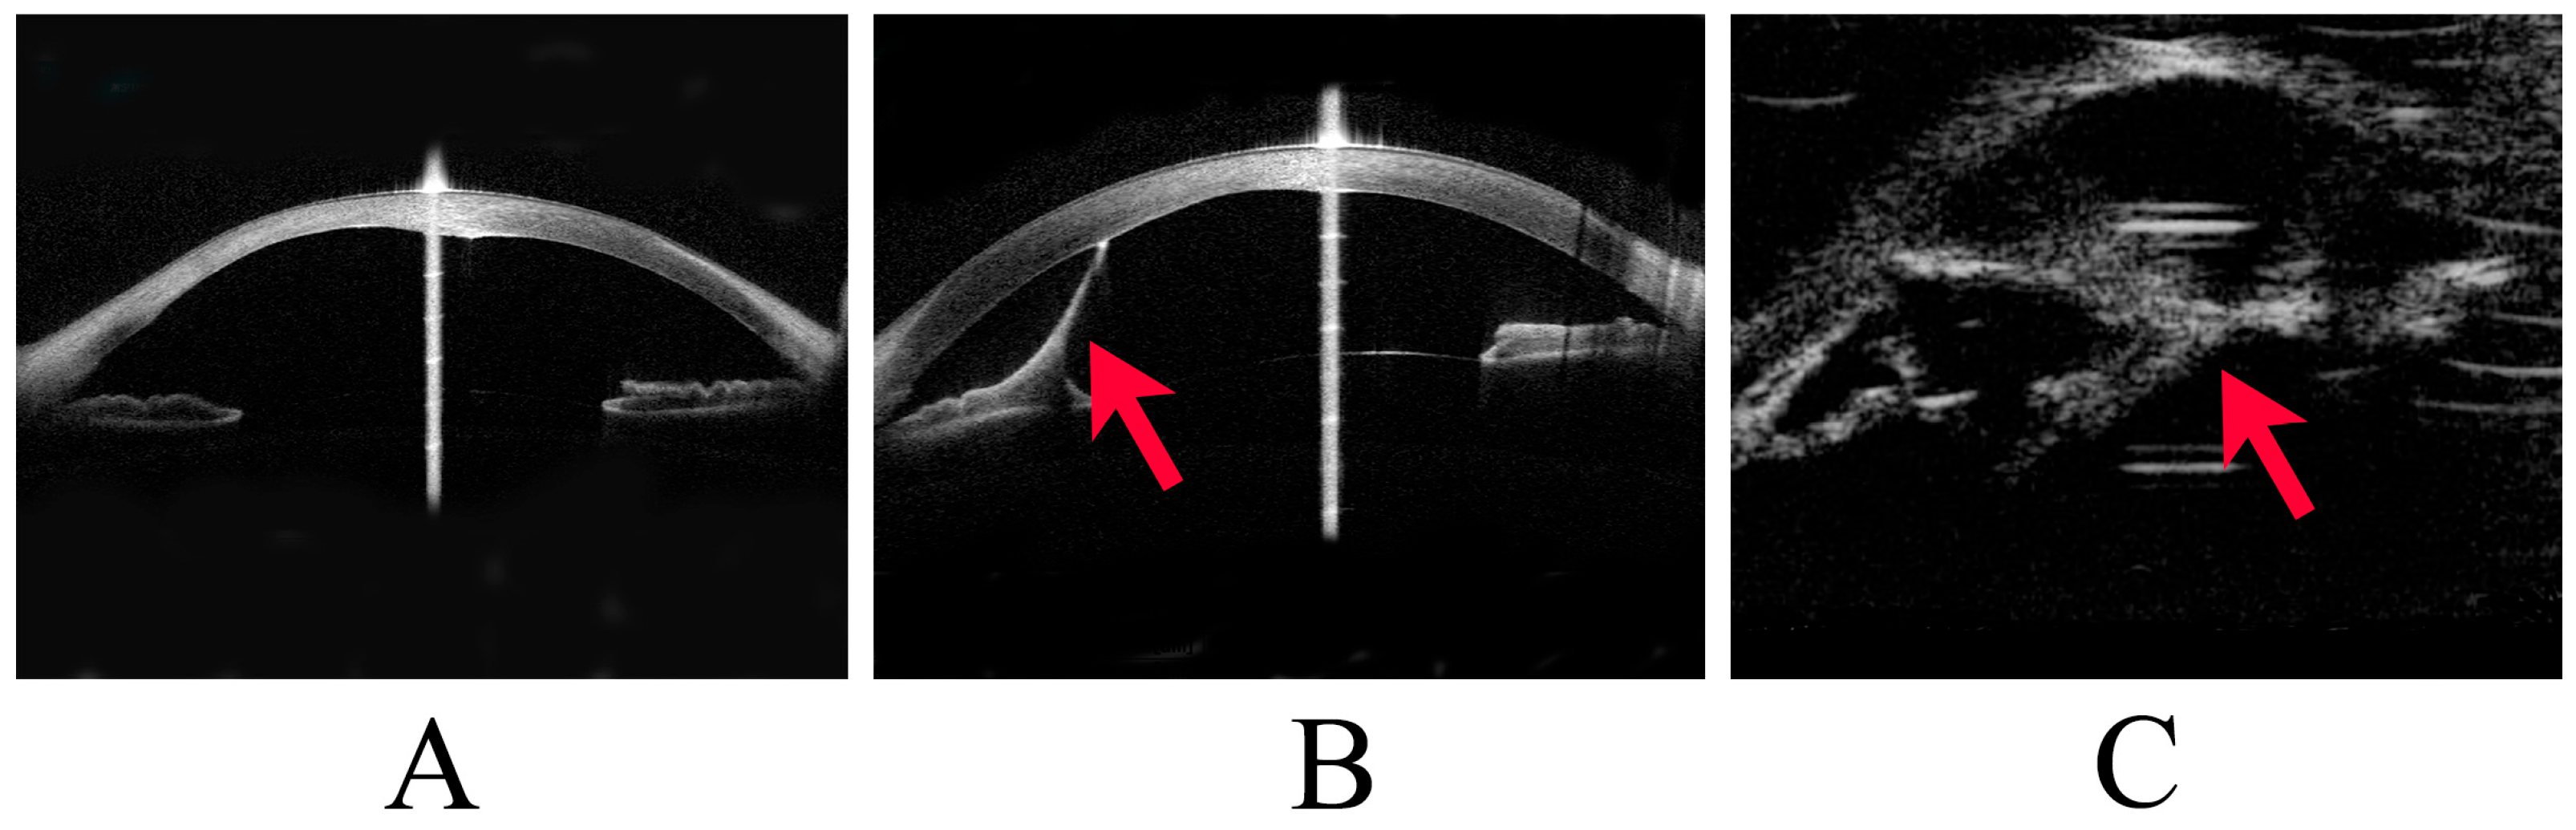

Peters anomaly was diagnosed clinically and classified as Stages 1, 2, or 3 according to the severity of anterior segment dysgenesis. Stage 1 was defined as the presence of a posterior corneal defect only; Stage 2 as a posterior corneal defect with corneal iris adhesion; and Stage 3 as a posterior corneal defect with lens abnormalities, including lenticulocorneal adhesion (Figure 1). Recently, patients with corneal iris adhesion and central corneal opacity are often classified as having type 1 Peters anomaly. In comparison, those with central corneal opacity associated with adhesion between the cornea and lens have been classified as having type 2 Peters anomaly [5,11]. However, this study classified the degree of anterior segment abnormality into Stages 1–3 to assess glaucoma management more accurately. In addition, cases of Peters anomaly with accompanying systemic disease were classified as Peters plus syndrome. Corneal staphyloma refers to the thinning of the cornea with a focal bulge.

Figure 1.

Stages of Peters anomaly. This image shows representative cases of Stage 1 to Stage 3 Peters anomaly. (A) Stage 1 Peters anomaly, with anterior segment optical coherence tomography (OCT) showing a posterior corneal defect. (B) Stage 2 Peters anomaly, with anterior segment OCT showing a strand (arrowhead) from the iris to the cornea and a posterior corneal defect. (C) Stage 3 Peters anomaly, with ultrasound biomicroscopy showing a strand (arrowhead) between the lens and the cornea.